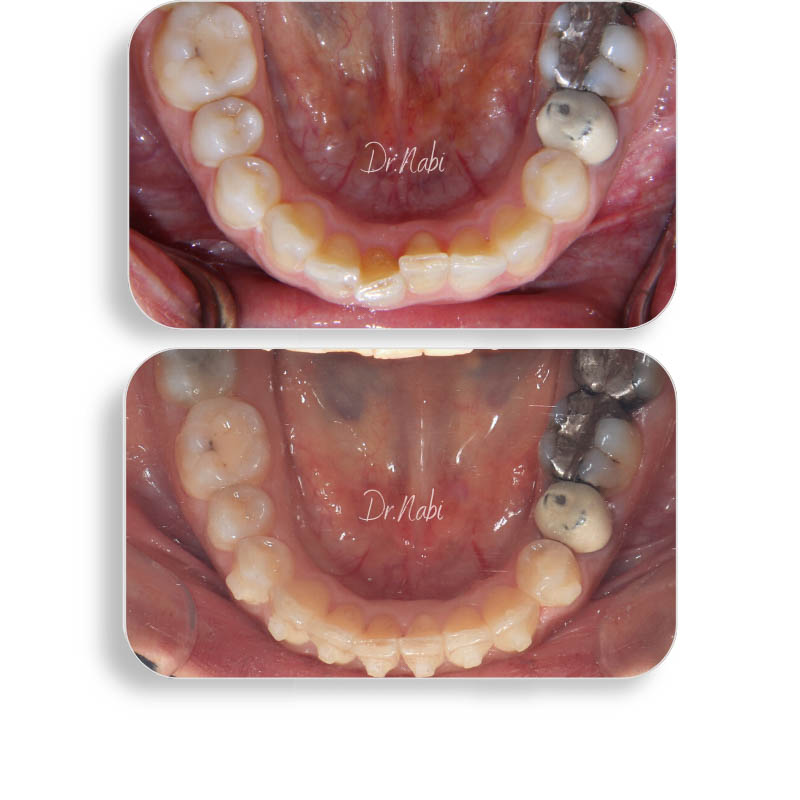

خانم 37 ساله که به جهت اصلاح نامرتبی فک پایین مراجعه کردند. در حدود 10 ماه با ارتودنسی نامرئی تمامی نامرتبی ها اصلاح شد.

درمان نامرتبی فک پایین با ارتودنسی نامرئی